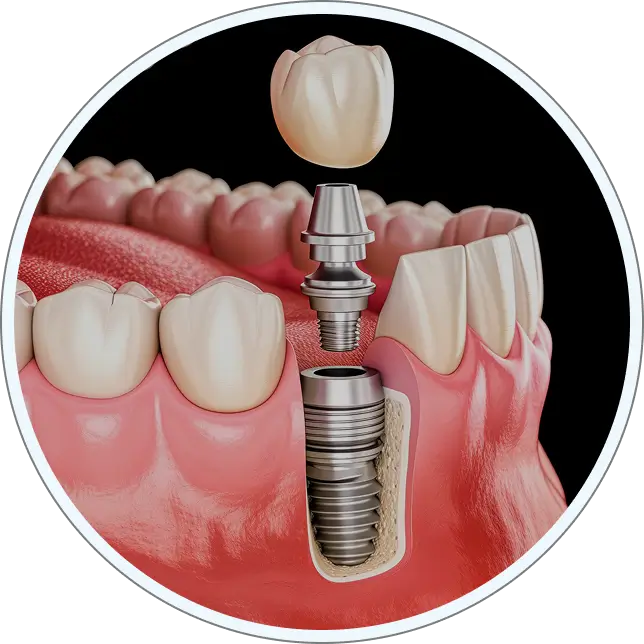

1 The Implant

Made of titanium, shaped like a screw or post, is placed into the jawbone.

2 Placing the abutment

Made of titanium, gold, or porcelain, this part attaches to the implant and connects it to the crown.

3 The Crown

Made of PFM, all-metal, or all-porcelain, the crown matches your teeth and is fixed to the abutment.